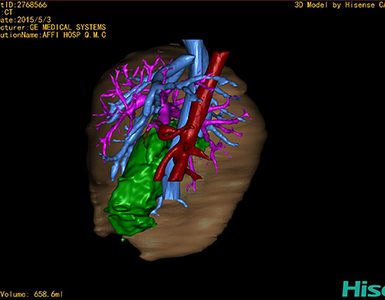

将0.625mm双源薄层CT资料的静脉期和动脉期Dicom格式文件导入海信CAS系统。

通过调节窗宽窗位调整CT序号,对肝实质,胆囊,下腔静脉,肿瘤,肝动脉、门静脉及肝静脉等进行三维重建;系统自动计算肝脏体积。

术前手术方案的规划。

术前三维重建:

重建图片